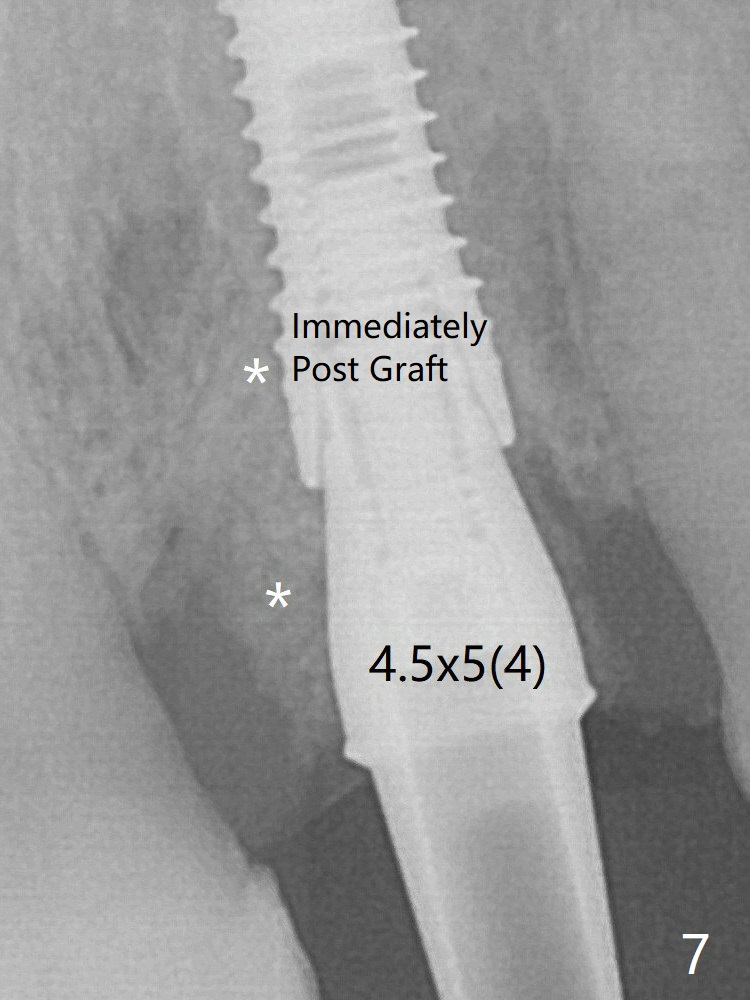

The mesial defect is filled with Vera Graft (Fig.7 *) and heals 1 year 4 months postop (Fig.11). The implant could be placed ~ 1 mm deeper (Fig.15).